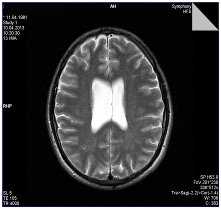

Отдельно можно рассмотреть феномен асимметрии МРТ - признаков аномалий головного мозга. Из таблицы 2 видно, что она касается дегенеративных процессов, представленных как в виде неравномерного расширения боковых желудочков (рис. 2), так и кровоснабжения мозга, в частности, аномалий строения виллизиева круга в виде трифуркаций внутренних сонных артерий, патологической асимметрии диаметра задних соединительных и передних мозговых артерий и асимметрии сигмовидных синусов.

Рисунок 2. Больной К., 32 года. Асимметрия тел боковых желудочков. МР томограмма в режиме Т2.